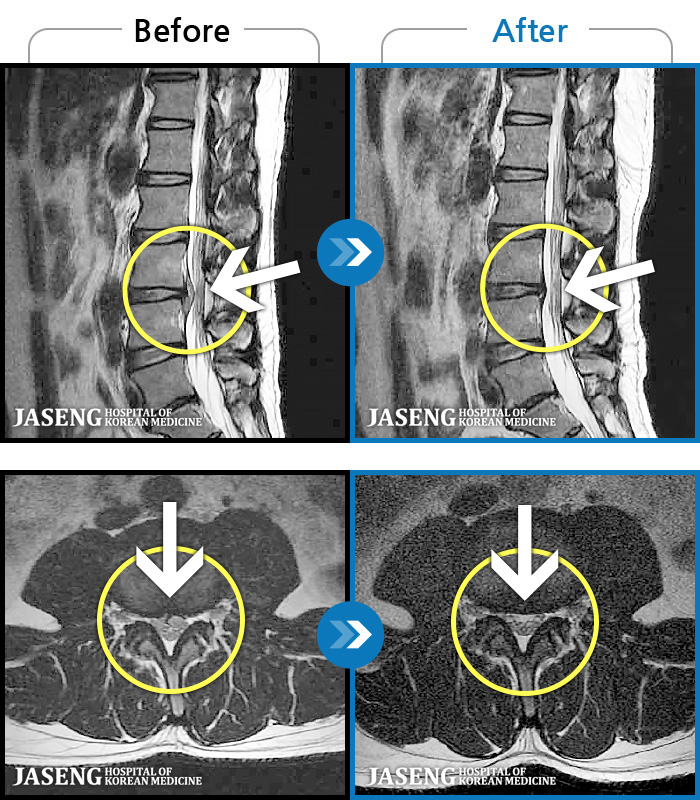

- MRI ġ

MRI ġ

1,237 MRI ũ ʸ Ȯϼ.